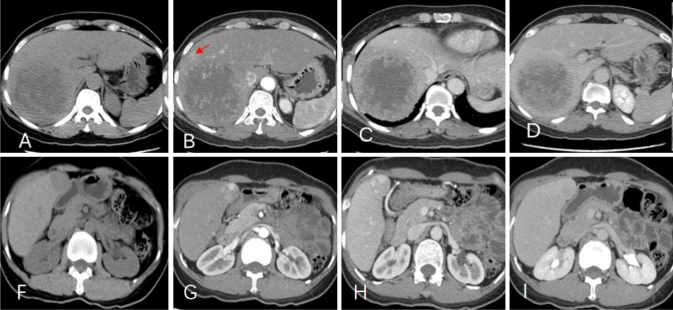

Case 1: A 46-year-old male cHCC-CC patient in the right lobe of the liver (Fig. 6a–d), recurrence 2 months after surgery.

Fig. 6.

a–d a 46-year-old male cHCC-CC patient with AST 61U/L, ALP 153U/L, MVI positive. a axial plain scan showed the tumor size > 5 cm and inhomogeneous; b peritumoral enhancement (red arrow shown) in arterial phase; c, d venous phase and delay phase showed the tumor necrosis > 75%, and tumor margins was unsmooth. f–i a 48-year-old female cHCC-CC patient with AST 27U/L, ALP 33U/L, MVI negative. f axial plain scan showed the tumor size < 5 cm; g no significant peritumoral enhancement in arterial phase; h, i in the venous phase and delay phase, the degree of tumor necrosis was less than 25%, and the tumor margin was smooth

Case 2: A 49-year-old female cHCC-CC patient in the right lobe of the liver did not recur after radical surgery in August 2014 until the end of the follow-up visit (Fig. 6f–i).